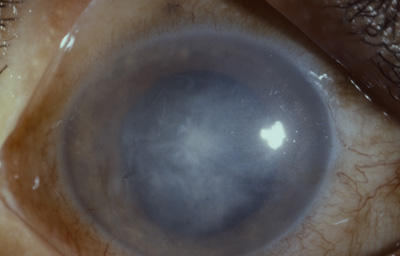

Paciente masculino quien realiza o cios varios, 32 años ( Tolima - Puerto Lopez) . Hace 2 meses picadura de avispa Cachicama en el OD - El aguijón fue extraído. Fue tratado con Maxidex durante 20 días

Al examen: OD Edema corneal con Queratopatía bullosa, “Atro a del Iris”, Opacidad subcapsular anterior;. Tensión ocular digital media. Secuelas tóxicas de picadura (Foto No12)

Foto 12 - Foto con edema total de la córnea, despigmentación del Iris y opacidad subcapsular anterior

En el OI: Antecedente de trauma craneoencefálico 20 años antes, con la rama de un arbol. Córnea con nubéculas múltiples puntiformes; Catarata subcapsular anterior y posterior en roseta. Tensión ocular 12, Recesión angular, polo posterior bien.

Se programa para Queratoplastia penetrante OD y Aspiración de catarata en el Ojo Izquierdo.- NO REGRESÓ